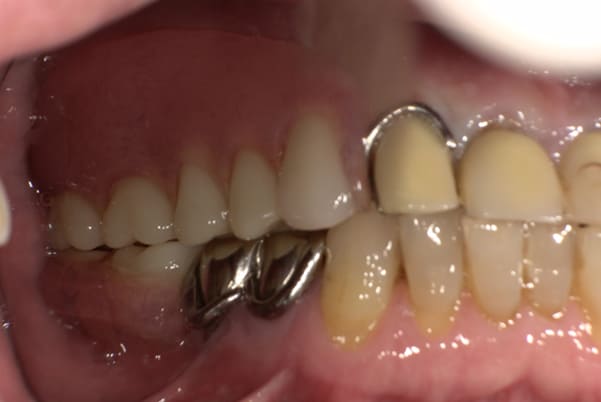

上の前歯が重度歯周病により動揺し、残せない状態のため、入れ歯も動揺がありました。

ご自身の歯に負担の少ないバネ、また見た目も改善

ご自身の歯に負担の少ないバネ

銀歯からセラミック歯に

バネをかける歯は繋げることで強度を増し、歯への負担を軽減し、歯の寿命を長くする設計へ。

バネがかかる歯の被せ物は、歯への負担を減らし、入れ歯が動きにくいようになる形態をあらかじめ付与することで、より入れ歯の機能が高まります。

治療を行う際、被せ物や入れ歯は、別々に考えるのではなく、一口腔単位としてお口全体のことを考え最良の治療計画を立てることが歯の寿命、機能効果を向上させるため、専門医としてこのことは常に心掛けて治療を行っています。